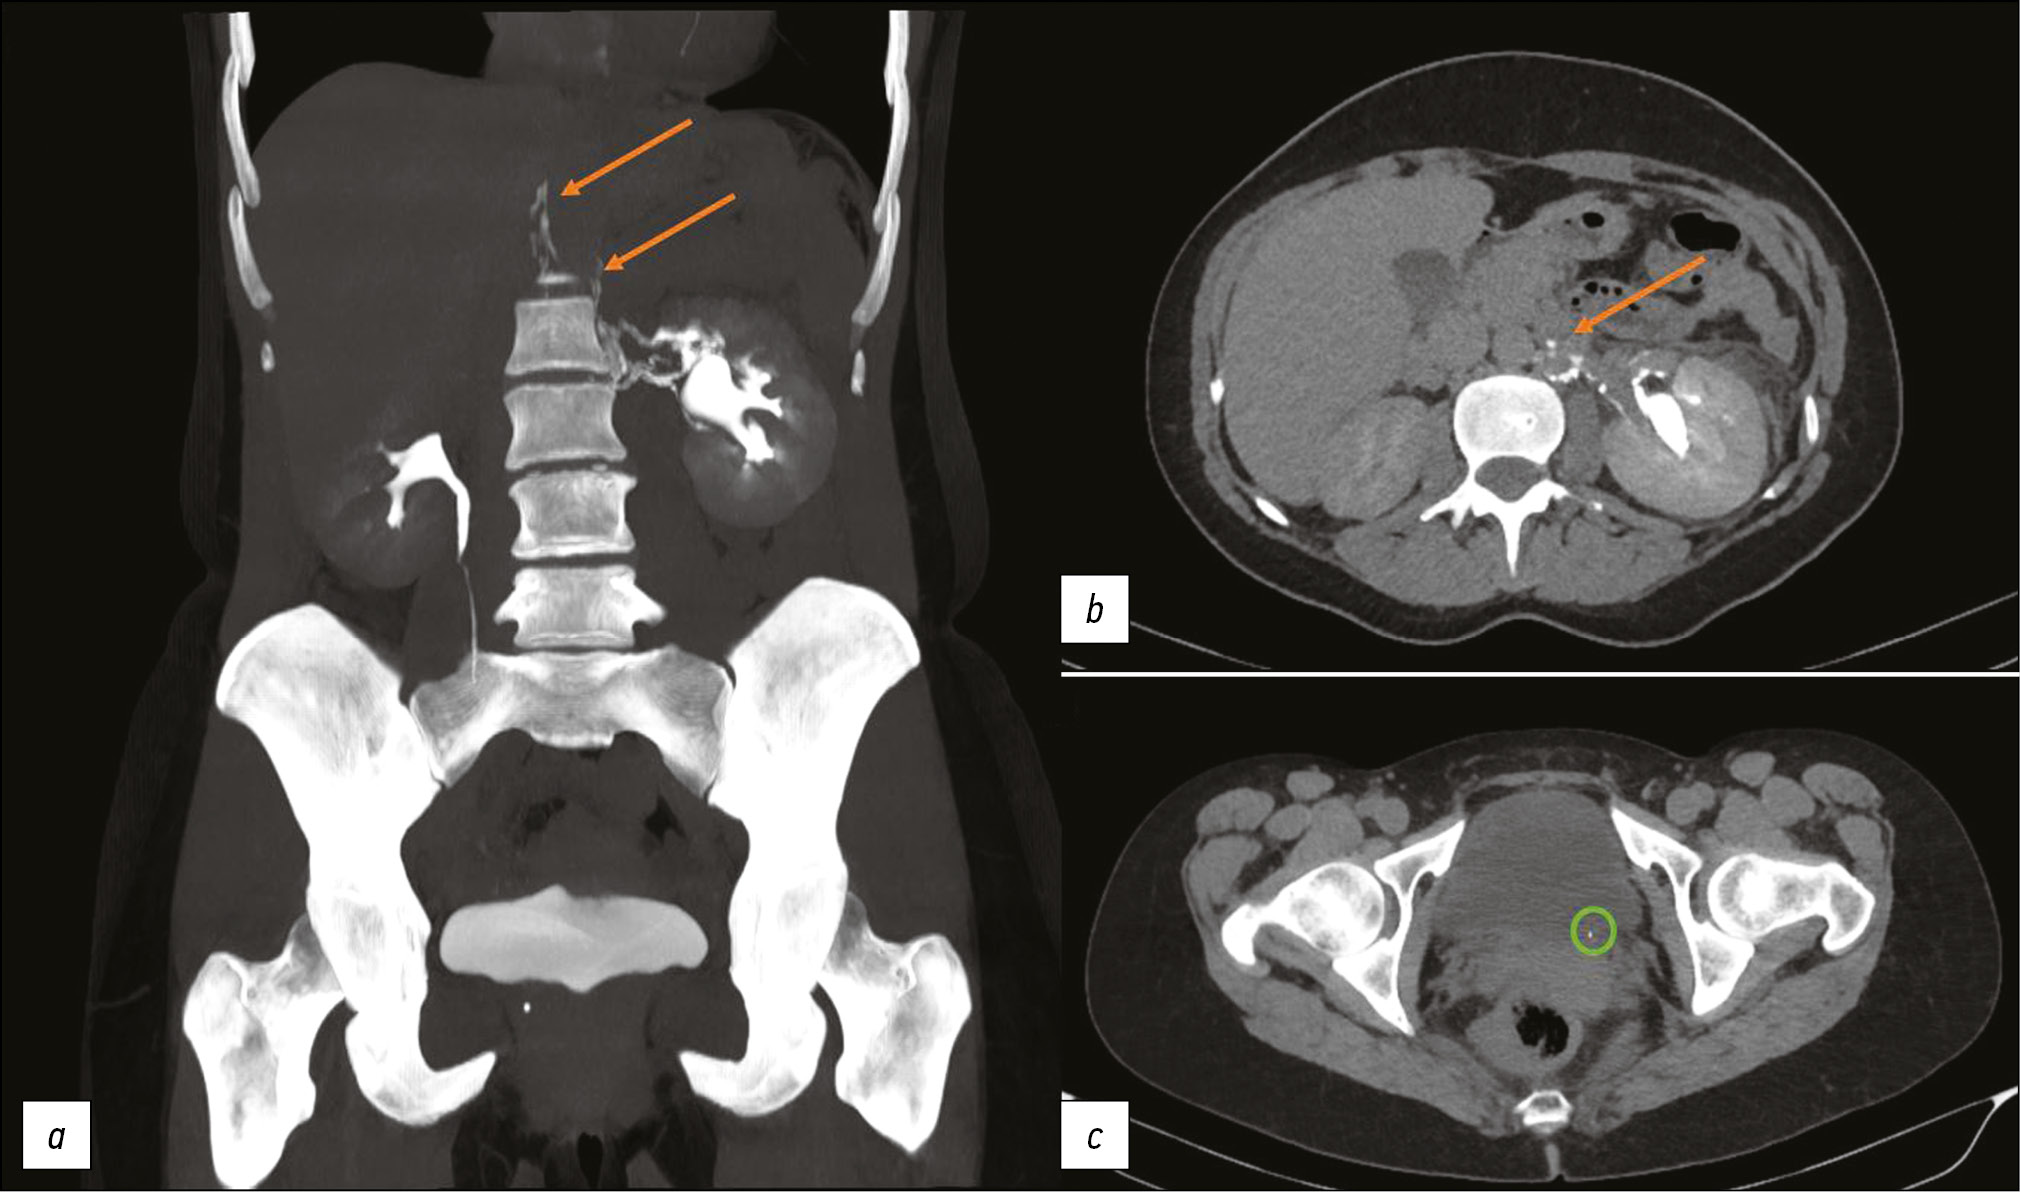

Computer tomography of uro-lymphatic fistulas associated with renal colic

This article presents two clinical observations of uro-lymphatic fistulas diagnosed by computed tomography. In both cases, the patients were admitted with symptoms of renal colic. Uro-lymphatic fistulas are a rare condition caused by the formation of a connection between the urinary and lymphatic systems, which is caused by, as a rule, lymphatic vessel obstruction due to parasitic infestation. Other causes may be radiation therapy, retroperitoneal trauma, and tumor sprouting. In the era before antibiotics, infectious processes such as xanthogranulomatous pyelonephritis and renal tuberculosis were common. Cases of uro-lymphatic fistulas formed against urolithiasis background are presented below. In the clinical cases presented, urine directly entered the lymphatic vessels through a uro-lymphatic fistula detected on contrast-enhanced computed tomography. Uro-lymphatic fistulas caused by impaired urine outflow due to blocked urinary tract are rarely detected since abdominal ultrasound is the diagnostic method of choice in renal colic. In the vast majority of cases, uro-lymphatic fistulas are treated conservatively and do not require surgical intervention. As a rule, the formed fistulas cease to exist when its root cause is successfully treated.

149-155